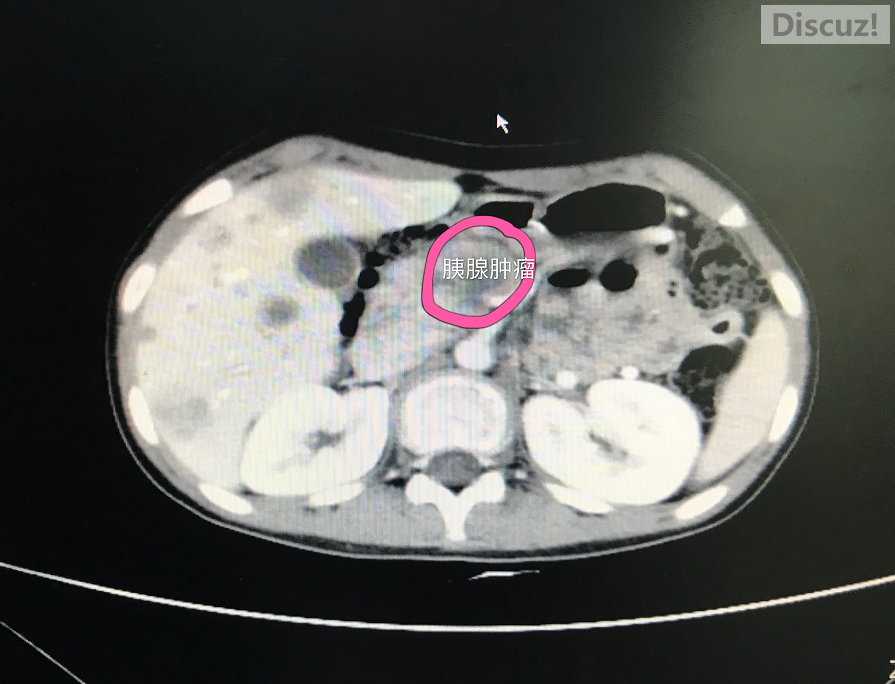

B超提示,小希胰腺有肿块。进一步检查确定:胰腺肿瘤晚期伴肝转移。“胰腺上的肿块3厘米左右。”接诊医生、该院小儿外科副主任医师林晓坤十分惋惜:肿瘤已经转移到肝脏。肝脏上都是密密麻麻的转移灶,有将近20个。腹腔淋巴结多处肿大。小希的病情已处于晚期,失去了手术机会,只能通过化放疗,但生存几率很小。